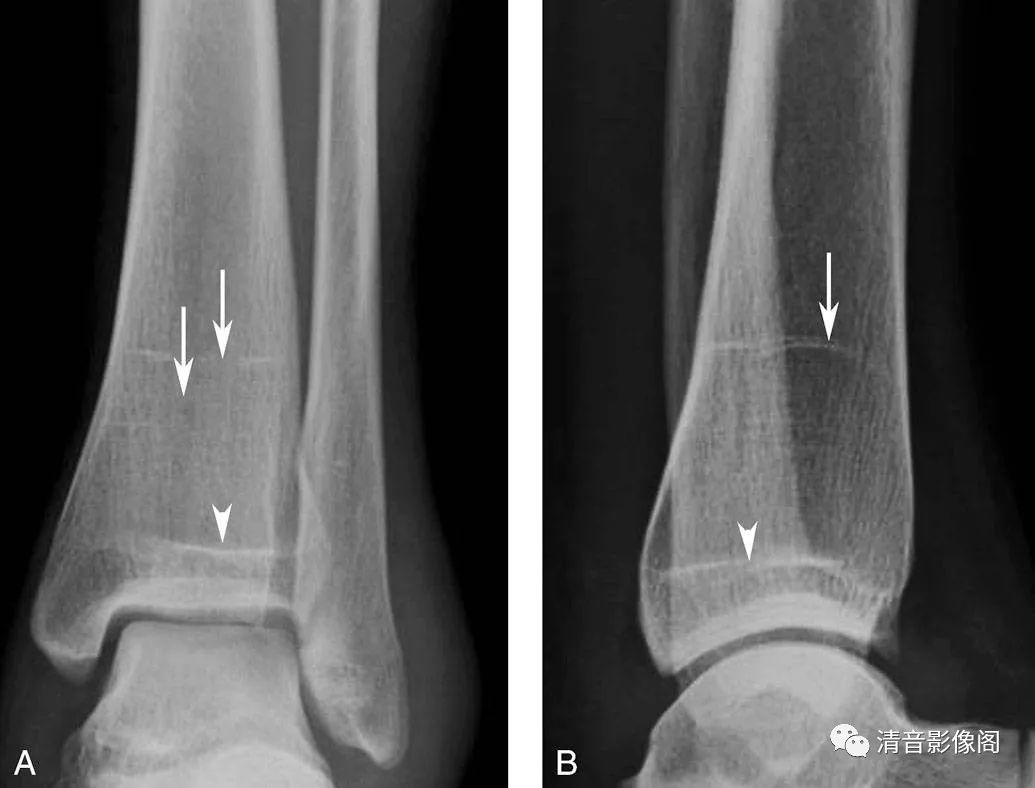

生长障碍线

A. 踝关节正位X线片;B. 踝关节侧位X线片。男,36岁。生长障碍线是由于暂时性生长紊乱,临时钙化带未能完全吸收和塑形形成的干骺端横行致密线(箭),多无病理意义。图中骨化的骺板影(箭头)有时可一直存在。